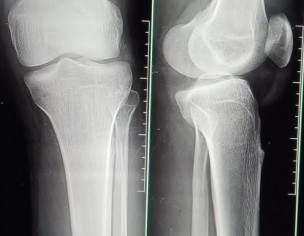

My fiance had an accident a month ago and then he had an x-ray but the bone was not broken at that time but still the pain was not getting less. So the injured leg is getting weak and he is not being weighed. he does not walk faslty and can't go up the give a good advice. Need your kind response.

Xray is ok get an MRI knee

There is no bone fractured but may be ligaments injury that won’t be visible in xray, so get checked up by Orthopedic surgeon and or get MRI done n share